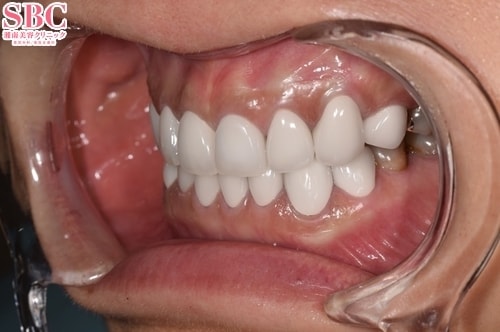

No.322025【美容歯科】上下16本プレミアムダイヤモンドセラミックで明るく整ったお口元に♪

施術後5ヶ月後

上の歯が欠けてしまったことと、虫歯や歯の変色などでお悩みのお客様です。テトラサイクリン歯と呼ばれ帯状に変色が見られます.

上の歯8本、下の歯8本のセラミック治療で、色、形の美しく整った自然な前歯に改善させていただきました♪